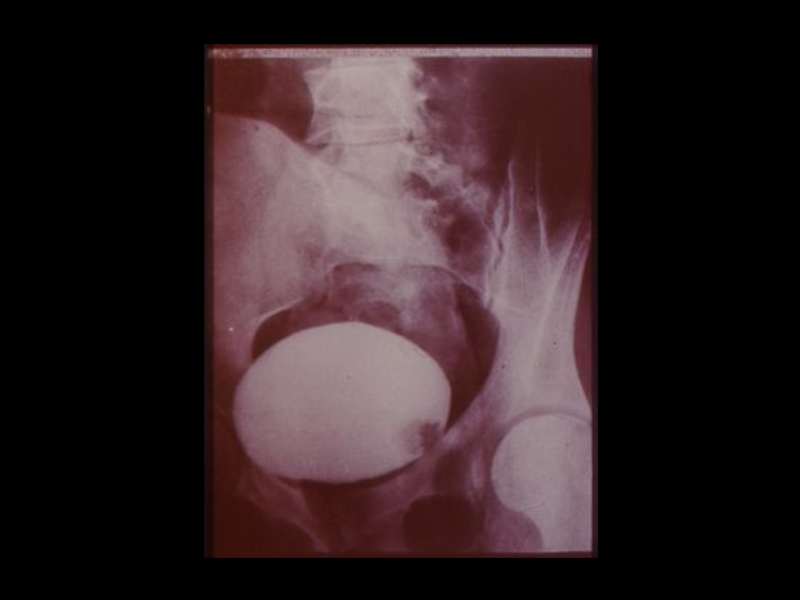

3. Специальные методы

(урография, бронхография, ангиография,

лимфография, пневмоартрография и другие)

Методы традиционной рентгенодиагностики:1. Общие методы   (рентгеноскопия, рентгенография)2. Частные методы   (флюорография, томография,

Слайд 37Задачи искусственного контрастирования органов:

1. Получение изображения органов , не обладающих

естественной контрастностью

2. Повышение разрешающей способности методов, за

счет повышения качества изображения и создания

эффекта «усиления»

3. Осуществление контроля при проведении

интервенционных мероприятий, проводимых с

помощью лучевых методик.

Задачи искусственного контрастирования органов:1. Получение изображения органов , не обладающих   естественной контрастностью2. Повышение разрешающей способности